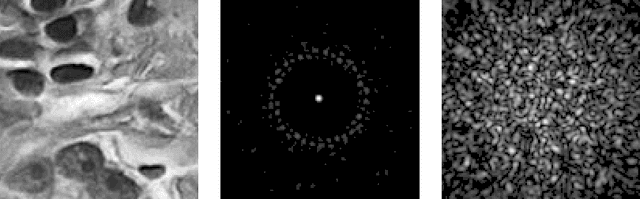

Abstract:The lensless endoscope (LE) is a promising device to acquire in vivo images at a cellular scale. The tiny size of the probe enables a deep exploration of the tissues. Lensless endoscopy with a multicore fiber (MCF) commonly uses a spatial light modulator (SLM) to coherently combine, at the output of the MCF, few hundreds of beamlets into a focus spot. This spot is subsequently scanned across the sample to generate a fluorescent image. We propose here a novel scanning scheme, partial speckle scanning (PSS), inspired by compressive sensing theory, that avoids the use of an SLM to perform fluorescent imaging in LE with reduced acquisition time. Such a strategy avoids photo-bleaching while keeping high reconstruction quality. We develop our approach on two key properties of the LE: (i) the ability to easily generate speckles, and (ii) the memory effect in MCF that allows to use fast scan mirrors to shift light patterns. First, we show that speckles are sub-exponential random fields. Despite their granular structure, an appropriate choice of the reconstruction parameters makes them good candidates to build efficient sensing matrices. Then, we numerically validate our approach and apply it on experimental data. The proposed sensing technique outperforms conventional raster scanning: higher reconstruction quality is achieved with far fewer observations. For a fixed reconstruction quality, our speckle scanning approach is faster than compressive sensing schemes which require to change the speckle pattern for each observation.